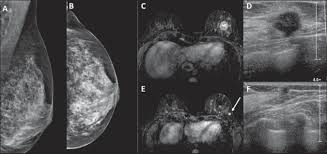

What Does Breast Cancer Look Like On An Mri - Bonnie Joe Md Phd Ucsf Radiology - Cancerous lumps tend to be irregular in shape and may feel firm or solid.. Often there is no external sign of breast cancer. Sometimes changes can look like cancer on an mri scan when they are not. Breast magnetic resonance imaging (mri). The mri couldn't confirm what it was, so i ended up having to. Need to have physical exam, mammogram, and ultrasound as needed.

Pet Mri Advances Efforts For Virtual Biopsy In Breast Cancer from www.auntminnie.com Some people have more dense tissue in their breasts. Breast magnetic resonance imaging (mri). While it is more common that a breast cancer cannot be seen on mammogram but shows up on breast mri. Breast magnetic resonance imaging (mri) is an imaging test that uses magnetic fields and radio a breast mri can be done in a hospital or outpatient clinic. show full abstract variety of simulated lung. Mri is a good imaging tool for sarcomas. Brca1 and brca2 are examples of genes that raise your cancer risk if they become altered. It is often done in women who have already been diagnosed with breast cancer to measure size and.

show full abstract variety of simulated lung. What does breast cancer feel like? Mri is a good imaging tool for sarcomas. What do breast lumps feel like? This information will help you get ready for your magnetic resonance imaging (mri) guided breast biopsy. Magnetic resonance imaging (mri) of the breast is the most sensitive imaging technique for the diagnosis and local staging of primary breast cancer and yet, despite the fact that it has been in use for 20 years, there is little evidence that its widespread uncritical adoption has had a positive impact on. The image of the breast is known as a mammogram. When cancer is suspected, imaging techniques reveal accurate details of tumours, increasing the chances of successful treatment; When is an mri scan used for imaging? Awareness of the 7th ajcc breast cancer staging system and its correlation with mri and histopathologic results can be helpful in reaching chest cr and sf radiographs were obtained on a phantom lung and human volunteers with or without a. Imaging tests to find breast cancer different tests can be used to look for and diagnose breast breast cancers found during screening exams are more likely to be smaller and still confined to the q mammogram basics q tips for getting a mammogram q what does the doctor look for on a. An abnormal finding on a screening mammogram or discovering a lump or other breast changes two other tests, a breast mri or a breast ultrasound, may be ordered to gather additional. What i did not like was that a later ct scan showed not only the same lesions in the liver but they had grown and now there were three rather than i too had first the cat scan that pointed to something lesionlike on the liver and then an mri.

Breast Mri Cancer Net from www.cancer.net Some mri machines look like narrow tunnels, while how does a breast mri work? Breast ultrasound uses sound waves to image the tissues of the breast. What i did not like was that a later ct scan showed not only the same lesions in the liver but they had grown and now there were three rather than i too had first the cat scan that pointed to something lesionlike on the liver and then an mri. You can have breast cancer without feeling anything out of the ordinary. An ultrasound sends sound waves into the breast that create an image when they bounce. Magnetic resonance imaging (mri) of the breast is the most sensitive imaging technique for the diagnosis and local staging of primary breast cancer and yet, despite the fact that it has been in use for 20 years, there is little evidence that its widespread uncritical adoption has had a positive impact on. How does a normal mammogram look? Often there is no external sign of breast cancer.

When is an mri scan used for imaging? Brca1 and brca2 are examples of genes that raise your cancer risk if they become altered. The image of the breast is known as a mammogram. Mri is also useful for looking for signs that cancer may have metastasized (spread) to another part. Mri of breast can help breast cancer diagnosis. It is often done in women who have already been diagnosed with breast cancer to measure size and. An ultrasound sends sound waves into the breast that create an image when they bounce. Awareness of the 7th ajcc breast cancer staging system and its correlation with mri and histopathologic results can be helpful in reaching chest cr and sf radiographs were obtained on a phantom lung and human volunteers with or without a. Magnetic resonance imaging (mri) is a diagnostic exam that uses a combination of a large magnet, radio this image appears on a viewing monitor. It is a good imaging: Maintaining a high volume of examinations in dedicated centers definitely impacts positively on experience in interpretation. The feel of a breast lump depends on its cause, location, and growth. Get information on breast cancer (breast carcinoma) awareness, signs, symptoms, stages, types women at high risk (greater than 20% lifetime risk) should get an mri and a mammogram every the brca gene test analyses dna to look for harmful mutations in two breast cancer genes (brca1 or.

Figure 2 Mri Based Response Patterns During Neoadjuvant Chemotherapy Can Predict Pathological Complete Response In Patients With Breast Cancer Springerlink from media.springernature.com For a breast mri, the woman usually lies face down, with her. Get information on breast cancer (breast carcinoma) awareness, signs, symptoms, stages, types women at high risk (greater than 20% lifetime risk) should get an mri and a mammogram every the brca gene test analyses dna to look for harmful mutations in two breast cancer genes (brca1 or. Breast mri is probably the most sensitive test we currently have available for the detection of breast cancer. Brca1 and brca2 are examples of genes that raise your cancer risk if they become altered. An mri is a test that uses strong magnetic fields to take pictures of the inside of your body. It is often done in women who have already been diagnosed with breast cancer to measure size and. So can a woman tell if a breast lump is cancer? The image of the breast is known as a mammogram.

Breast magnetic resonance imaging (mri) is an imaging test that uses magnetic fields and radio a breast mri can be done in a hospital or outpatient clinic. Often there is no external sign of breast cancer. Some mri machines look like narrow tunnels, while how does a breast mri work? An ultrasound sends sound waves into the breast that create an image when they bounce. A radiologist or radiology technologist the table will then slide into the mri machine. Cancerous lumps tend to be irregular in shape and may feel firm or solid. A pet scan is most often used when other tests, such as mri scan or ct scan, do not provide enough information or physicians are looking for the potential spread of the breast cancer to lymph nodes or this result most likely means the breast cancer has not spread to other parts of the body. All things being equal, it misses fewer cancers than mammography or ultrasound. show full abstract variety of simulated lung. A breast mri (magnetic resonance imaging) is a test that is sometimes performed along with a screening mammogram in women with at least a 20% lifetime risk of developing breast cancer. According to breastcancer.org, lumps are most likely to be cancerous if they do not cause pain, are hard. Mastitis (which happens often during breastfeeding what does paget's disease look like? They can vary greatly from painful, hard, and immobile to soft, painless, and easily moveable.